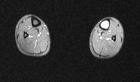

C.G. – 21 year old white female college lacrosse player with four month history of left shin pain worsened by activity. Physical exam demonstrates TTP overlying distal left tibia, extremity NVI.

Zoom image: Radiological image Radiological image.